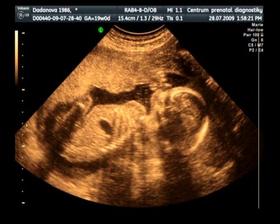

Naše maličké

Dne 15. 12. v 5:40 se nám narodil syn Jurášek. Vážil krásných 3500g a měřil ukázkových 50 cm. A je to nejkrásnější kluk na světě : )